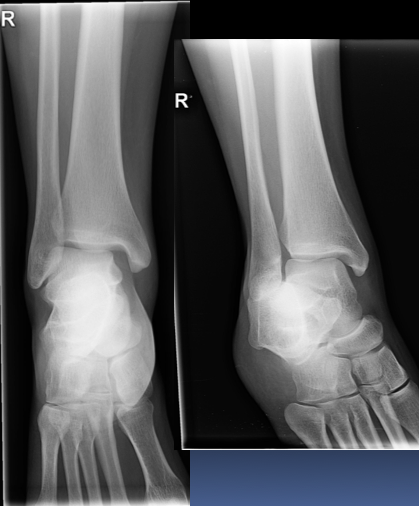

A 30 year old woman presented to the ED with right ankle pain after a fall. She was struggling to walk. Her ankle was swollen and tender on examination. Movement was limited due to pain.

AP and lateral fibula:

What is a maisonneuve fracture?

A combination of a fracture of the proximal fibula together with an unstable ankle injury (widening of the ankle mortise on x-ray)